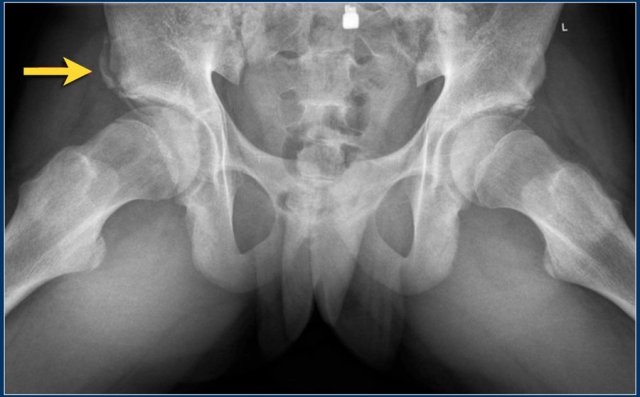

Avulsion injuries

Avulsion injuries of the pelvis are a frequent cause of hip pain in adolescents involved in sports.

Because at this age the tendons are generally stronger than the apophyses, strong muscle contraction can result in apophyseal avulsion fractures.

Avulsion injuries can be acute or chronic.

Typical avulsion injury of the anterior inferior iliac spine at the insertion of the rectus femoris tendon.

Typical avulsion injury of the right ischial aphophysis.